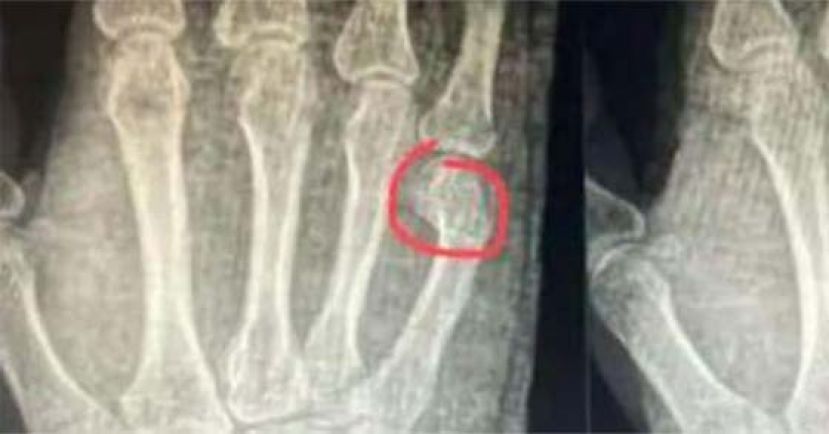

医生初步检查发现,吴先生的右手掌明显肿胀、淤青和明显的压痛。X光检查显示,他右手第五掌骨远端骨折,断端明显移位,需要住院治疗。

医生表示,他骨折的位置让闭合复位与固定比较困难,有骨折移位、畸形愈合的风险,出院后需及时复诊。